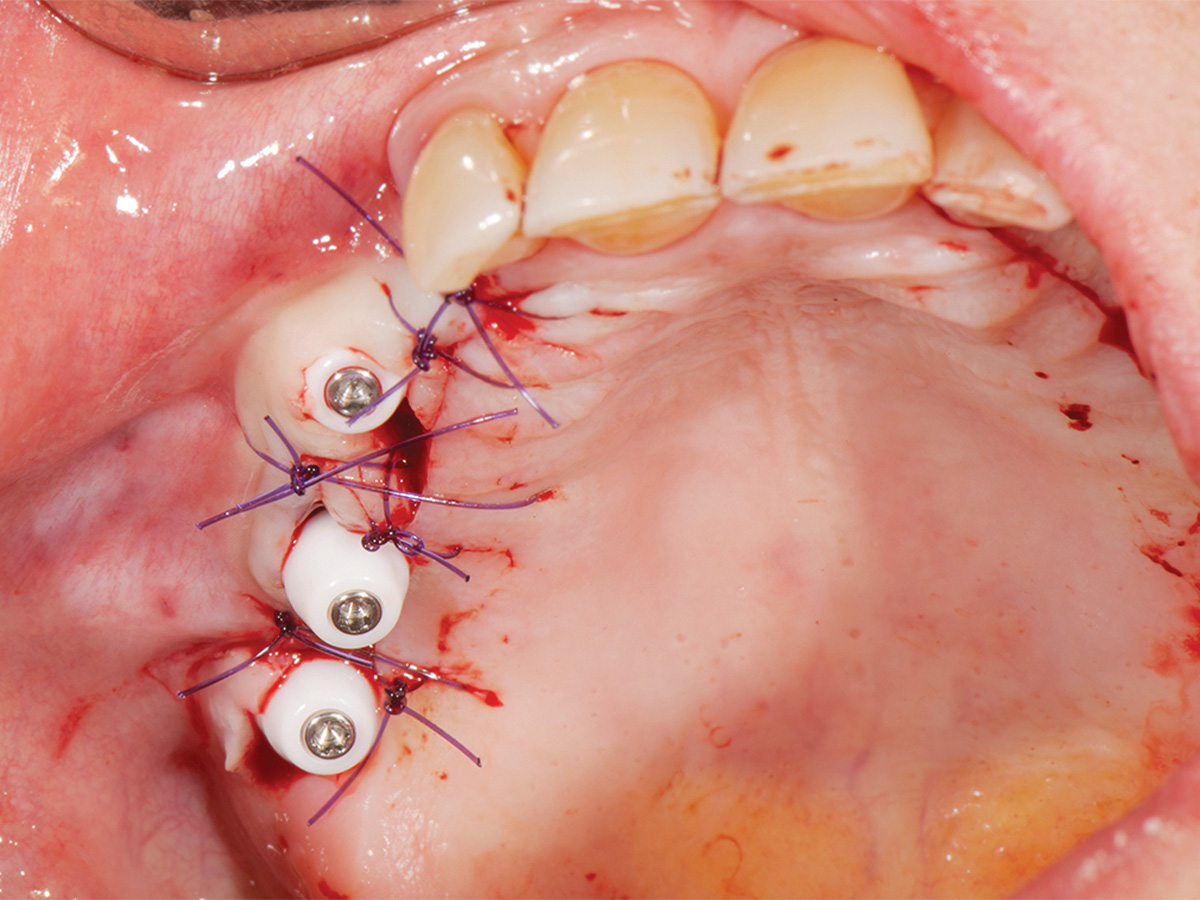

Abbildung 7

Einsetzen der Gingivaformer nach vier Monaten.

Abbildung 8

Wundverschluss, Okklusalansicht.